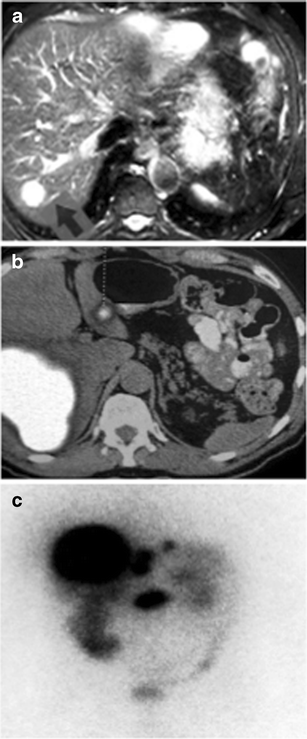

a MRI liver in 2004 showing one of the lesions which was hyperintense with a typical ‘light-bulb’ appearance on plain T2-weighted images. b FDG-PET scan showing uptake in the liver and pancreatic lesions with regional lymph node involvement. c OctreoScan confirming metastatic pancreatic neuroendocrine tumor

In 2007 the patient underwent a further reassessment for recurrent episodic abdominal discomfort. Upper endoscopy at this time confirmed persistent esophagitis with no frank ulceration; the previous changes of Barrett’s esophagus had resolved on long-term PPI. In January 2008 he was admitted to a tertiary referral centre for an acute exacerbation of abdominal pain. Physical examination revealed a febrile patient with mild tenderness over the right lower quadrant. Routine blood tests revealed a raised white cell count of 11.4x109/L (normal: 4.4–10.1x109/L) with neutrophilia, normal renal function and electrolytes including calcium; mildly elevated serum alkaline phosphatase of 123 U/L (normal: 42–110 U/L) and aspartate transaminase of 55 U/L (normal: 15–38 U/L), and normal bilirubin and clotting profile. Plain abdominal X-ray revealed a fecal-loaded colon with prominent small bowel loops. Computed tomography (CT) of the abdomen and pelvis was performed to exclude diverticulitis; this revealed a 10 cm heterogenous mass spanning segments V, VI, VII and VIII of the right lobe of the liver, a second intrahepatic mass occupying segments VI and VII adjacent to it, and a pancreatic mass at the uncinate process with regional mesenteric lymphadenopathy. Tumor markers including alpha-fetoprotein (AFP), prostate specific antigen (PSA) and Ca 19.9 were normal; carcinoembryonic antigen (CEA) was slightly raised to 7.4 ng/ml (normal: < 5 ng/ml). The patient then underwent positron emission tomography/computed tomography (PET-CT) with 18-fluorodeoxyglucose (FDG), which showed hypermetabolic lesions in the liver, pancreas and mesenteric lymph nodes (Fig. 1b). Ultrasound-guided biopsy of the liver mass confirmed a low-grade neuroendocrine tumor; immunohistochemistry for synaptophysin, chromogranin and CD56 was positive. Other markers, including inhibin, c-kit, AFP, HEPA, CK7 and CK20, were negative.

Further neuroendocrine workup was performed after stopping PPI for two weeks. Fasting serum gastrin remained elevated (240 pg/ml; normal <113 pg/ml), with less marked elevations of chromogranin A (247 ng/ml; normal <160 ng/ml), and somatostatin (25 pg/ml; normal <22 pg/ml). Fasting plasma glucose, insulin, C-peptide and glucagon, and urinary vanillylmandelic acid (VMA) and catecholamines were normal, but 24-hour urinary 5-hydroxyindoleacetic acid was raised. Gastric acid output studies were not performed. Somatostatin receptor imaging (OctreoScan) showed intense uptake in the uncinate process of the pancreas, and in the right lobe, segment II, III and caudate lobe of liver, compatible with a neuroendocrine tumor rich in somatostatin receptors (Fig. 1c).

Second, the delay in diagnosis of this case from the time of symptom onset is typical of PPI-masked gastrinoma. This iatrogenic complication—in which, ironically, an established ZES supportive therapy [12, 13] is used for symptom relief without knowledge of the etiologic diagnosis, culminating in eventual diagnosis of more advanced disease with shorter average 5-year survival, perhaps reflecting a lead time effect—should be a matter of serious professional concern. In the present case the diagnosis of gastrinoma was masked by PPI-dependent reversion of hyperacidity, leaving only the nonspecific syndrome of intermittent abdominal pain and borborygmi. Indeed, so minimally symptomatic was the PPI-treated patient for several years that the early radiologic detection of liver metastases was misinterpreted, and the final diagnosis of malignancy was only made in response to painful liver capsular distension by massive tumor progression 4 years later. Since half of all ZES presentations occur in the absence of detectable liver metastases [14], early recognition of hypergastrinemic symptoms prior to carcinomatosis would seem the only feasible pathway to cure.

The suboptimal sensitivity and specificity in diagnosing pancreatic neuroendocrine tumors by conventional imaging techniques also adds to the diagnostic dilemma. For example, the sensitivity of MRI in detecting these tumors is reported to vary between 29% to 57% only [19, 20, 21]. MRI visualization of islet cell tumors, which have a rich arterial blood supply [21], depends on their hypervascularity relative to the surrounding normal pancreatic tissue [17], but it is difficult to distinguish them from other vascular lesions including hemangiomas. In the present case, tumors already present on MRI liver in 2004 were misinterpreted as benign hemangiomas (Fig. 1a). Curiously, FDG-PET is reputed to be less useful in well-differentiated slow-growing neuroendocrine tumors [18, 19] but was of value in our case; newer positron-emitter radiopharmaceuticals including 11C 5HTP and 11C L-DOPA appear more sensitive [20]. Somatostatin receptor scintigraphy is superior to ultrasound, CT, MRI, and FDG-PET in terms of both sensitivity and specificity [22], though 11C 5HTP-PET may prove even more sensitive.